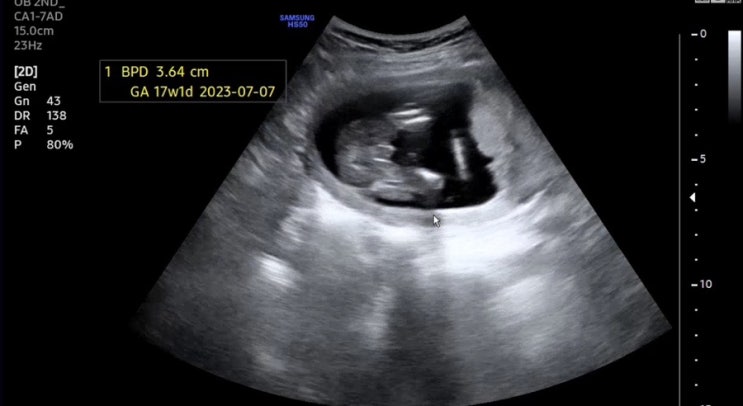

각도법은 과학인가 둘째도 아들 확정이다 ㅎㅎ 존재감 뿜뿜하는 17주1일차 초음파 - 내가 아둘맘이라니 허...